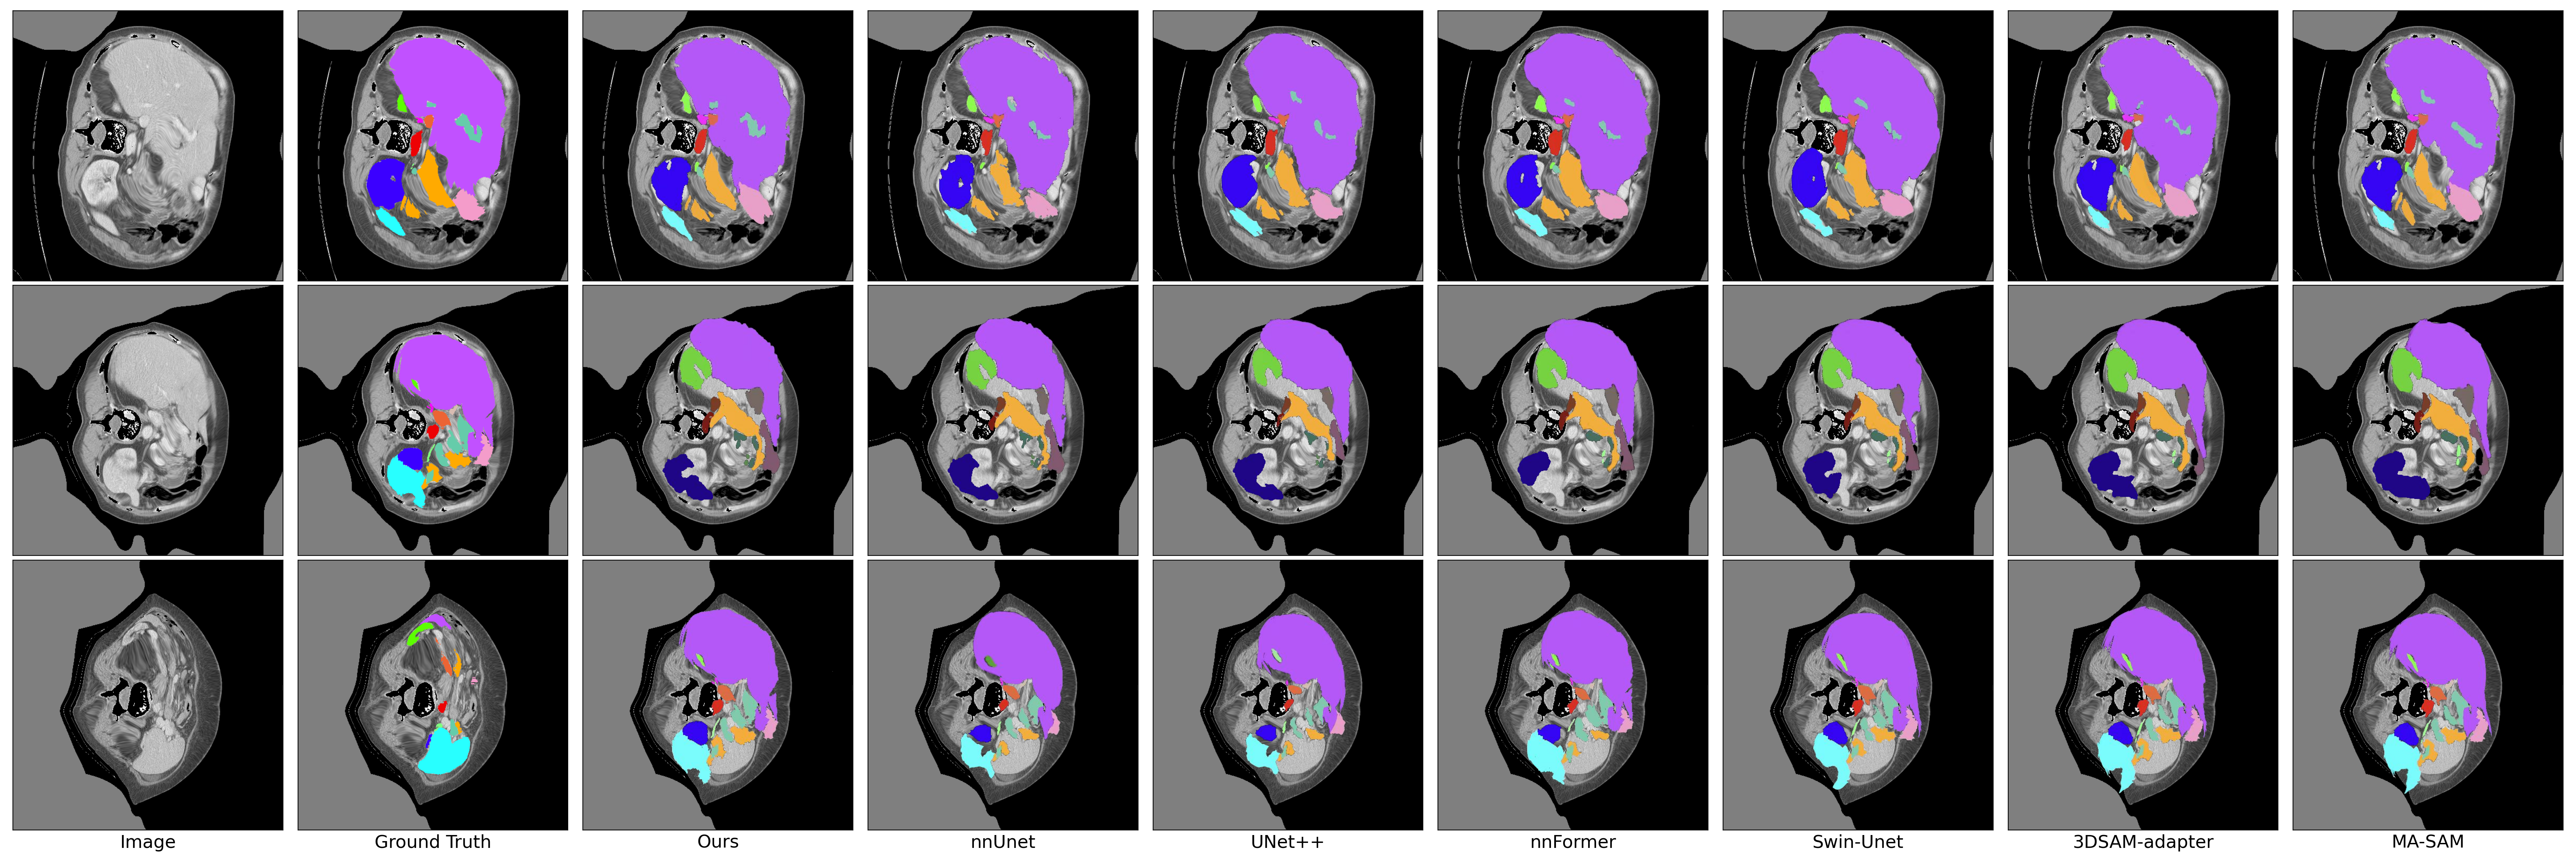

Refer to caption

Figure 4: Qualitative visualization of segmentation results generated from our Ref-SAM3D method and other state-of-the-art methods on BTCV dataset.

In the domain of multi-organ segmentation, we do experiments on BTCV dataset, the Ref-SAM3D approach demonstrated exceptional capability. Specifically,in the BTCV dataset shown in Table III, it achieved a DICE score of 97.1% for the spleen, outperforming all other methods. The left and right kidneys attained DICE scores of 96.1% and 94.9%, respectively. The esophagus achieved a DICE score of 85.2%, surpassing other methods, while the liver and stomach achieved scores of 97.3% and 94.1%, respectively. Furthermore, Ref-SAM3D showed its strengths in handling complex anatomical structures, such as the pancreas and aorta, achieving DICE scores of 87.5% and 92.3%, respectively. In terms of Hausdorff Distance (HD) evaluation, Ref-SAM3D also excelled, with an average HD value of 2.34, underscoring its superior boundary precision. Figure 4 shows qualitative visualizations on BTCV tasks. From the qualitative visualization results, Ref-SAM3D demonstrates superior performance in multi-organ segmentation tasks. The method accurately identifies and segments boundaries between different organs, maintaining high segmentation precision even in cases with blurred organ boundaries or complex anatomical structures. Notably, Ref-SAM3D maintains stable segmentation performance for both small organs like the pancreas and elongated structures such as the aorta, further validating the reliability of the quantitative evaluation metrics.